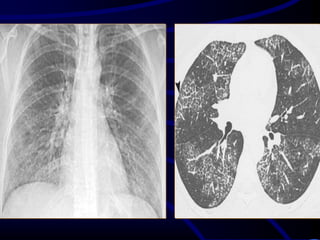

Bronchiectasis

Bronchiectasis is defined as localized bronchial

dilatation. (signet-ring sign)

bronchial wall thickening

lack of normal tapering with visibility of airways

in the peripheral lung

mucus retention in the broncial lumen

associated atelectasis and sometimes air

trapping

Signet-Ring Sign

A signet-ring sign represents an axial cut of a dilated bronchus

(ring) with its accompanying small artery (signet).

Tram Tracks

Bronchial dilation with lack of tapering .